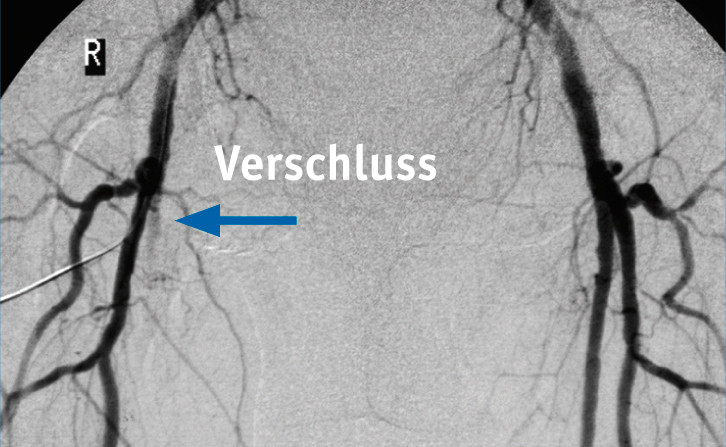

Neben dieser sich schleichend entwickelnden PAVK über die Jahre hinweg gibt es einen wenn auch seltenen akuten Bein-Infarkt, bei dem potenzielle Amputationsgefahr besteht, erklärt Lawall. »Dabei kommt es zu einem kompletten Verschluss der Arterie, etwa durch ein thrombosiertes Aneurysma oder einen Thrombus in der Beinarterie, und das lässt das ohnehin unterversorgte Gebiet absterben. Das beobachten wir häufiger nach einer Bypass-Operation oder nach Implantation eines Stents. Diese können sich plötzlich zusetzen und die Blutversorgung massiv beschneiden.«

Mit Hilfe eines Katheters lässt sich das verengte Gefäß wieder weiten. Dabei wird ein Führungsdraht mit einem Ballonkatheter an seiner Spitze über die Leiste in die betroffene Beinarterie eingeführt und bis zur Verengung vorgeschoben. Der Ballonkatheter wird in die Mitte der Verengung platziert und dort mit Druck aufgeblasen. Der Dehnvorgang kann Schmerzen verursachen, die aber nach der Entleerung des Ballons sofort wieder verschwinden. Der Ballon drückt die Kalbablagerungen in die Gefäßwand – die Verengung ist beseitigt und das Blut kann wieder ungehindert fließen. Bei komplizierteren oder längeren Gefäßverengungen wird zusätzlich eine röhrchenförmige Gefäßstütze (Stent) aus Metall oder Kunststoff ins Gefäß eingesetzt, damit die Kalkablagerungen nicht mehr ins Gefäßinnere zurückfallen. Auch arzneimittelbeschichtete Stents und Ballons werden eingesetzt. So bleibt die begradigte Engstelle länger offen. Diese endoskopischen Methoden sind einer Operation oft vorzuziehen. Bei hohem Leidensdruck und geeigneter Gefäßmorphologie sind invasive Verfahren gemäß Leitlinie bereits ab Stadium II möglich.